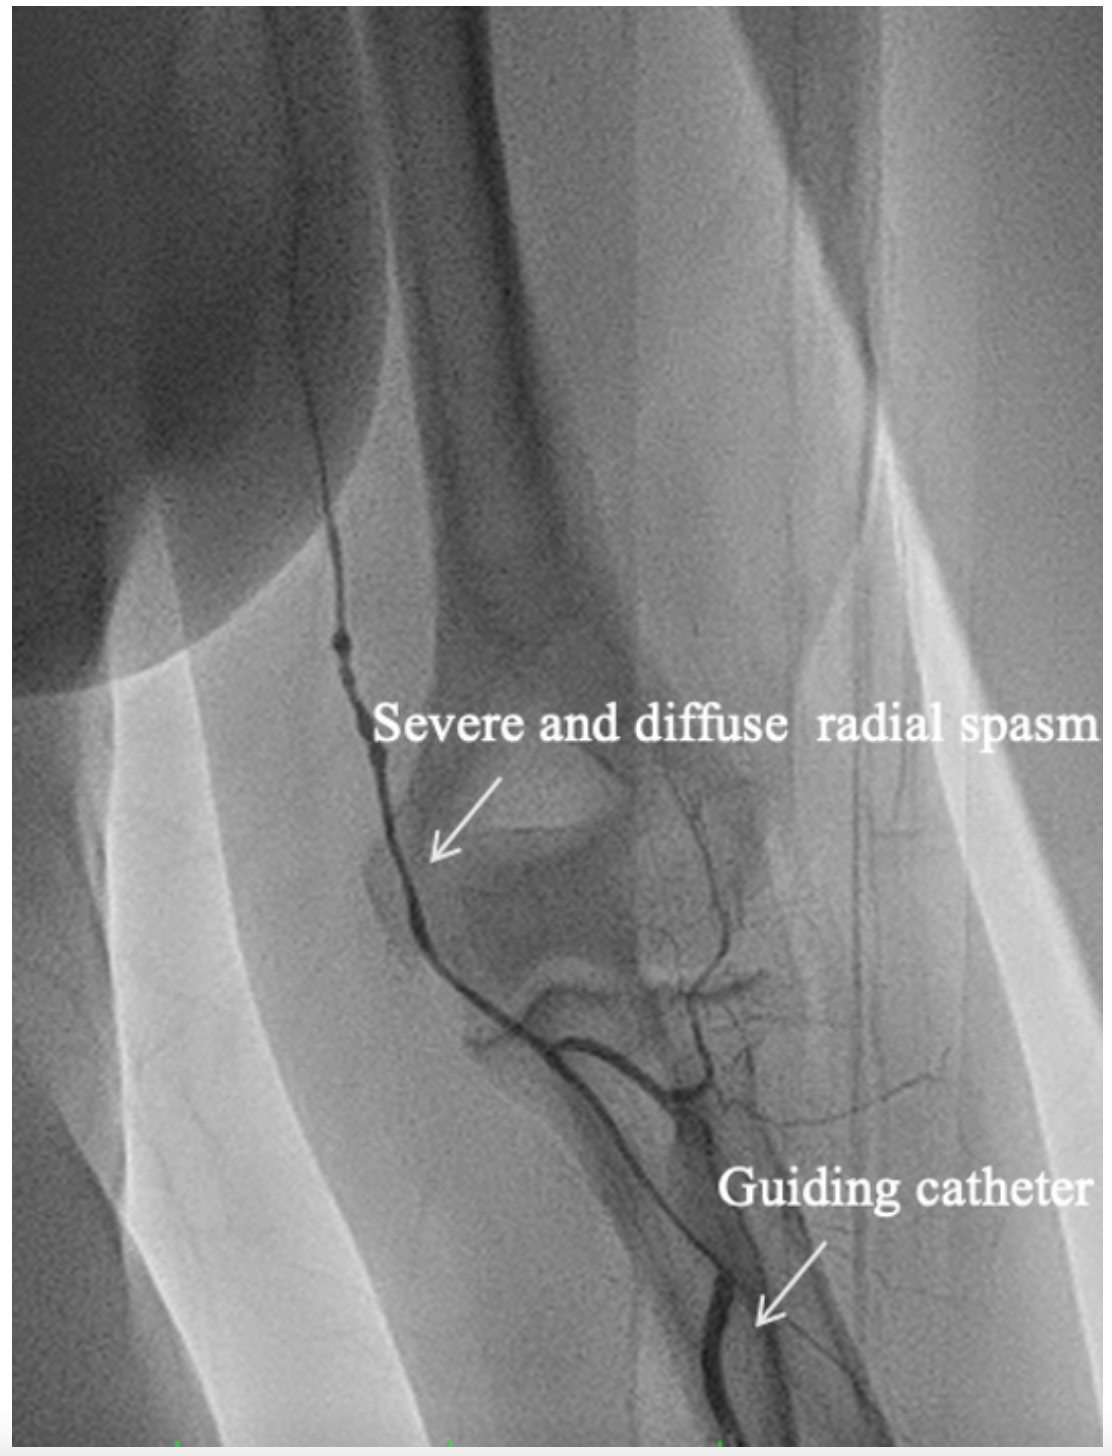

Example 2: Severe diffuse and resistant RA spasm. A 68-year-old female was admitted for elective PCI to the left anterior descending (LAD) coronary artery. A 6-Fr EBU 3.5 guiding catheter was selected upfront but could not be advanced beyond the elbow.

Contrast angiography revealed severe and diffuse RA spasm (Figure 4). A spasmolytic cocktail was administered without success. A standard .035˝ guidewire was advanced to the aortic root and a 4-Fr MP was inserted in the 6-Fr EBU guide catheter. The entire system was advanced using the MiCAT technique without any resistance, enabling successful completion of the LAD PCI via the intended TRA site.